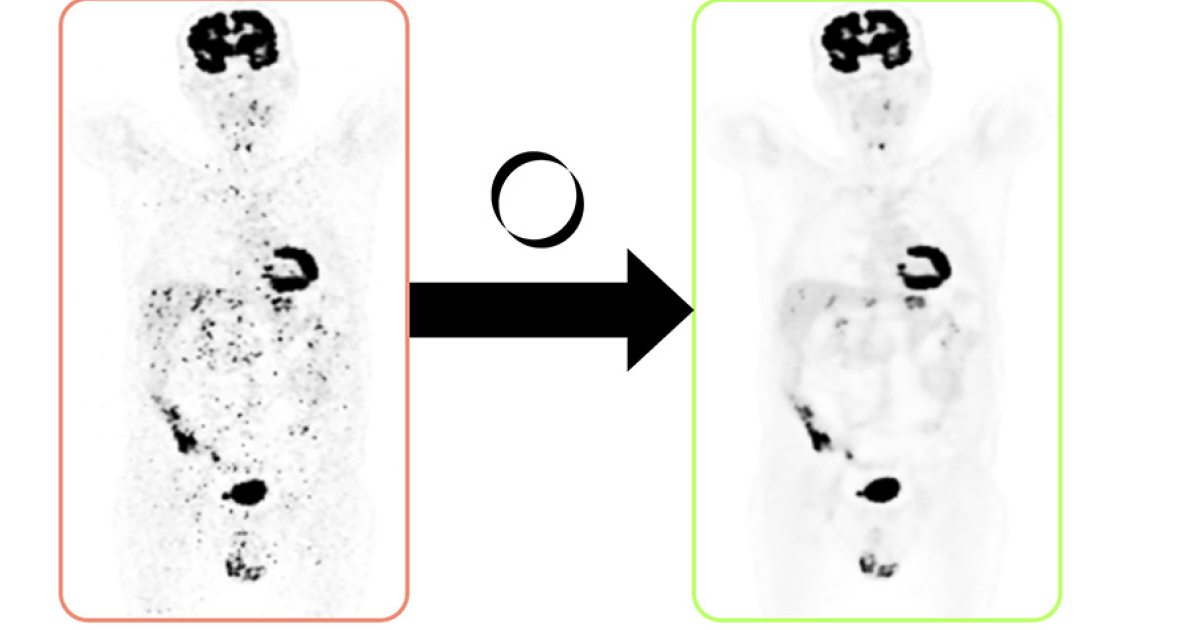

Hoe het Gentse softwarebedrijf dat allemaal concreet maakt, laten we liever uitleggen door co-founder Maarten Larmuseau. “Wij hebben software voor nucleaire geneeskunde ontwikkeld die ziekenhuizen toelaat om met behulp van minder radiotracer medische beeldvorming van dezelfde kwaliteit te genereren. Want hoewel de radioactieve vloeistof die gebruikt wordt heel beperkt is, blijft het in zekere zin schadelijk voor de patiënt. Hoewel minder radiotracer voor ruizige beeldkwaliteit zorgt, waardeert onze software die op.”

Momenteel krijgen patiënten gemiddeld 1 tot 2 millisievert (mSv) aan radioactieve vloeistof toegediend, aanzienlijk meer dan de dagelijkse natuurlijke stralingsdosis van 0,004 mSv. Hoewel deze dosis veilig is, blijft de straling niet zonder risico's. Maarten: “Als je minder tracer gebruikt, krijg je meer ruis in de beelden, wat kan leiden tot foutieve interpretaties. Onze software analyseert en verbetert die beelden zodat artsen dezelfde nauwkeurige diagnoses kunnen stellen.”